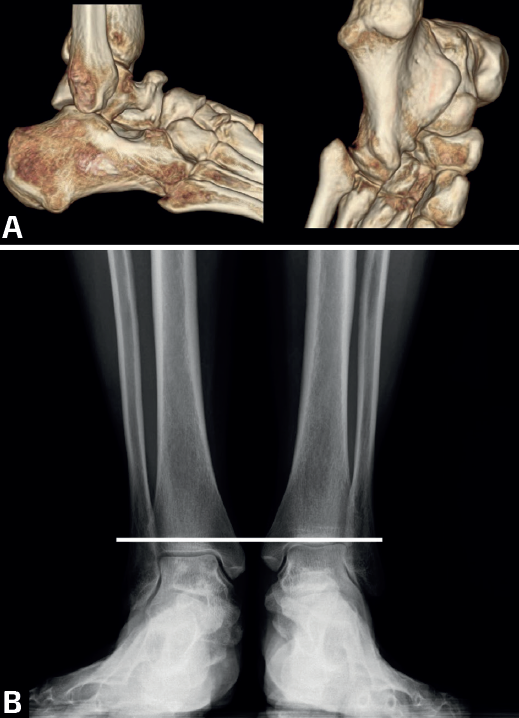

mact.1701.fs2403007-figura3.png

Figura 3. Paciente de la figura 1 con coalición calcaneocuboidea bilateral sintomática. En las imágenes 3D de la tomografía computarizada se aprecia con detalle la coalición, el osteofito dorsal talar y una desaxación entre la columna lateral y medial (A). El pie derecho era más valgo que el izquierdo, como se pone de manifiesto en la proyección anteroposterior de ambos tobillos en carga (B), con menor altura de la cúpula astragalina al suelo. También era el más sintomático y no mejoró suficiente con plantillas.